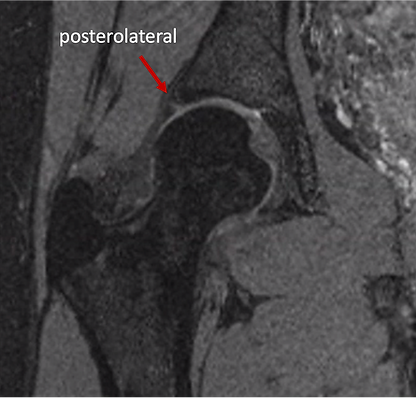

Ein Labrumriss tritt häufig als sekundäre Folge einer Überbelastung des chondrolabralen Übergangs auf, die durch ein Impingementsyndrom oder Hüftinstabilität verursacht wird.

Meist entsteht die Schädigung durch eine knöcherne Ursache, die im Laufe der Jahre zu einer Überbelastung und letztlich zu einer Ruptur des Labrums führt. Diese Ursachen müssen sorgfältig analysiert und erkannt werden, um die zugrunde liegende Problematik zu verstehen. Denn eine Naht des Labrums ohne Behandlung der auslösenden Ursache würde vermutlich zu einem erneuten Riss und einem Versagen der Therapie führen.

Häufig ist ein Labrumriss ein Hinweis auf eine Konflikt- oder Instabilitätsproblematik in der Hüfte. Deshalb empfehlen wir nach einer solchen radiologischen Diagnose die Vorstellung bei einem Hüftspezialisten, der Erfahrung in der Behandlung sowohl von Hüftdysplasie als auch von Hüftimpingement hat.